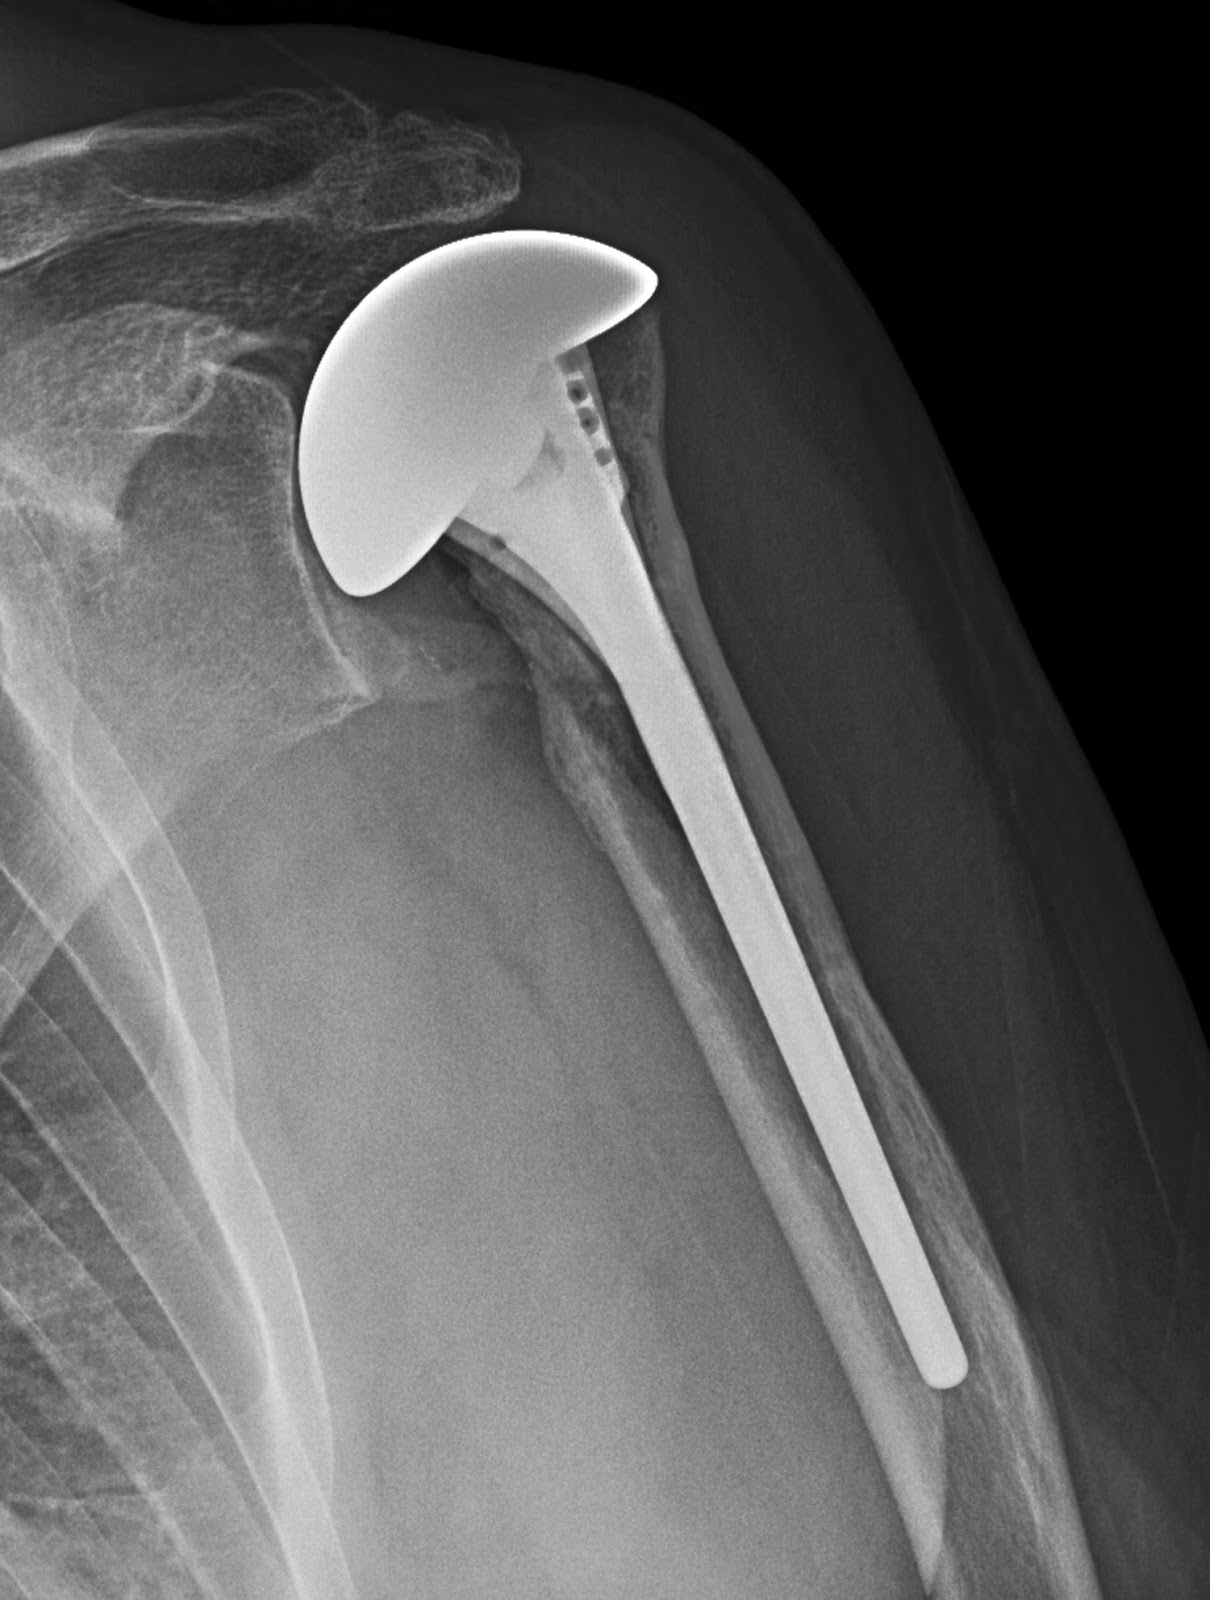

From cambridgeshoulder.co.uk

Fig 42. Resurfacing Shoulder Arthroplasty Cambridge Shoulder Is Shoulder Replacement Painful Progress after shoulder replacement surgery is different for everyone, but you can expect: A shoulder replacement is a procedure that tries to eliminate the source of pain and dysfunction by replacing damaged parts of the shoulder joint with artificial components. Total shoulder replacement, also known as total shoulder arthroplasty, is a procedure where portions of the bones in the shoulder. Is Shoulder Replacement Painful.